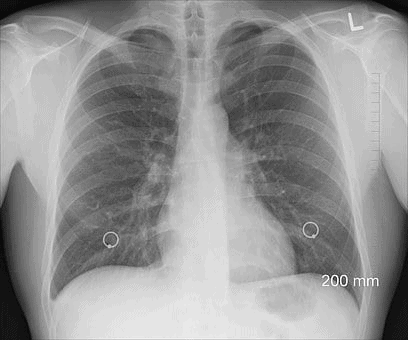

Pulmonary contusion is a condition resulting from trauma or a direct blow to the chest. The condition mainly emanates from car crashes or falls. Victims who sustain these injuries have a difficult time moving on with their regular life. Some of the common symptoms to look for after a car accident include:

When force is applied to the lungs, blood vessels get damaged. Victims who experience chest injuries mostly develop pulmonary contusion. When such a condition is left unchecked, this can lead to life-threatening consequences.